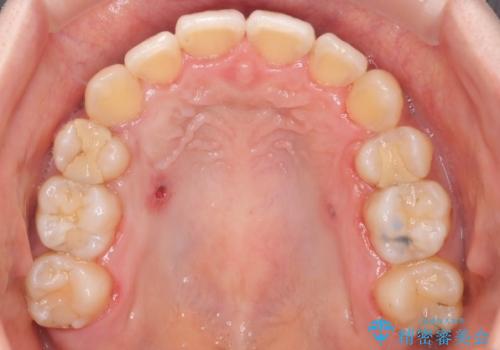

ガタガタの抜歯矯正を裏側ワイヤーを使っての目立たない矯正

- 八重歯とガタガタを主訴に来院されました。

目立たないワイヤー矯正を希望されたので、上下左右のはを1本ずつ抜歯して、ハーフリンガル(上顎だけ裏側)にて矯正をすることにしました。